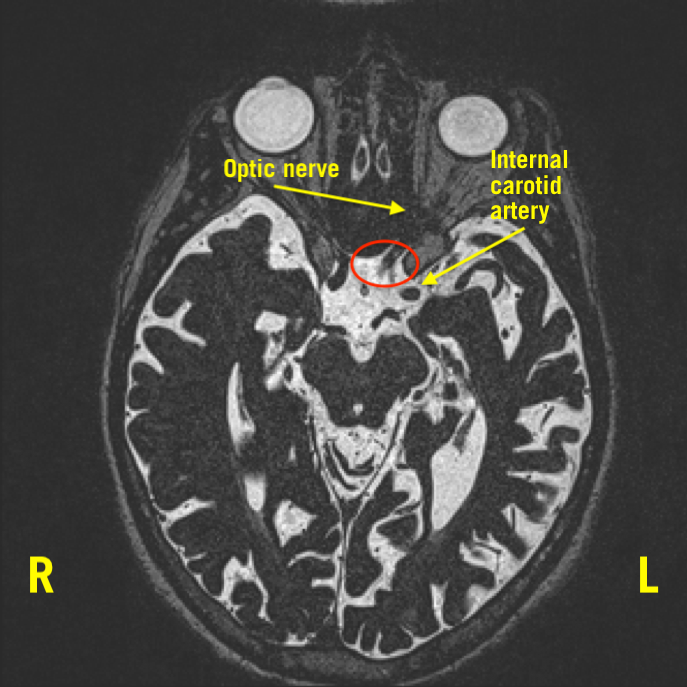

MRI of the orbit was significant for a flattening of the left optic nerve anterior to the optic chiasm, with a prominent flow void from the left anterior cerebral artery (ACA) crossing over the superior aspect of the nerve. Additionally, a mild mass effect was seen inferiorly from the internal carotid artery (ICA), contributing to the compression of the left optic nerve (Figures 1-3).

Figure 2. Harder to appreciate, the ICA was also compressing the optic nerve inferiorly. The red circle notes compression.